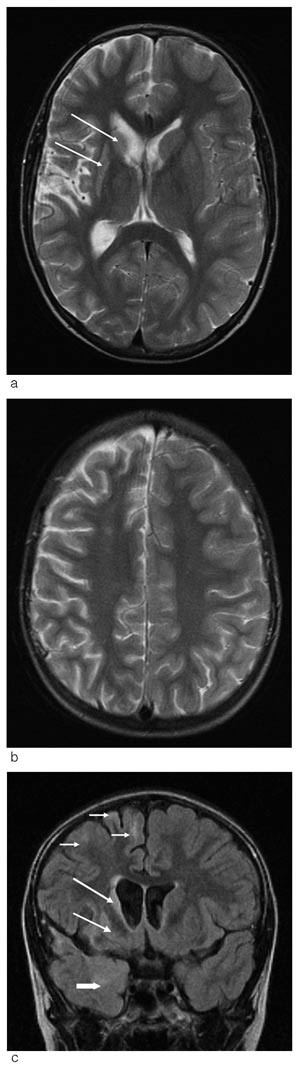

Spinalpunksjon viste ingen pleocytose, normalt proteinmønster og ingen oligoklonale eller polyklonale bånd i gammafraksjonen. Det var heller ikke holdepunkt for virusinfeksjon eller metabolsk sykdom. Ny cerebral MR viste betydelige patologiske forandringer (fig 1).

Dette MR-funnet kombinert med intraktabel epilepsi og progredierende hemiparese er diagnostiske kriterier for Rasmussens encefalitt. Funksjonell hemisfærektomi av den affiserte hemisfæren er foreløpig det eneste behandlingsalternativet som fjerner eller reduserer anfallene og kan stoppe videre progrediering av nevrologiske utfall ved denne tilstanden. Slik behandling bør derfor vurderes så snart diagnosen er avklart.

EEG viser vanligvis langsom, multifokal epileptiform aktivitet over den affiserte hemisfæren (4). Cerebral MR viser økende atrofi av den affiserte hemisfæren, primært i perisylvisk område, samt forstørret sideventrikkel på samme side. I tillegg kan man se høysignalområder både i grå og hvit substans samt atrofi av nucleus caudatus (5). Diagnosen bekreftes ved funn av perivaskulære lymfocytiske infiltrasjoner, knuter av mikroglia og mikrogliaproliferasjon (3). Hjernebiopsi er ikke nødvendig for å stille diagnosen. En rekke differensialdiagnoser som primært affiserer den ene hjernehalvdelen eller medfører epilepsia partialis continua må overveies (tab 1).